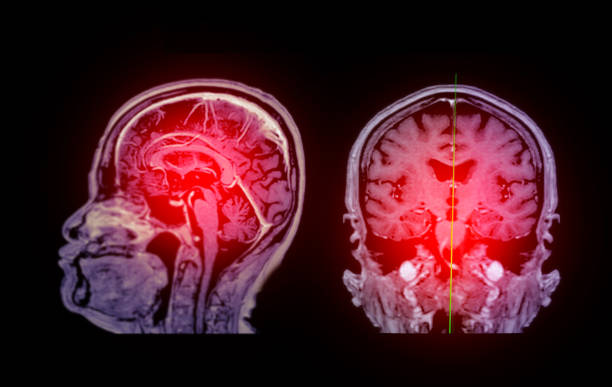

缺血性腦卒中,又稱腦梗死,是一種因腦部血液循環(huán)障礙導(dǎo)致的腦組織壞死疾病。它給患者帶來的不僅是身體上的痛苦,更是心理上的巨大壓力。

間充質(zhì)干細(xì)胞是一種具有多向分化潛能的細(xì)胞,能夠分化成多種類型的細(xì)胞,包括神經(jīng)細(xì)胞。因此,干細(xì)胞治療腦卒中中具有廣闊的應(yīng)用前景。通過將這些干細(xì)胞注射到患者體內(nèi),可以期望它們能夠分化成神經(jīng)細(xì)胞,替代受損的腦組織,從而恢復(fù)患者的神經(jīng)功能。